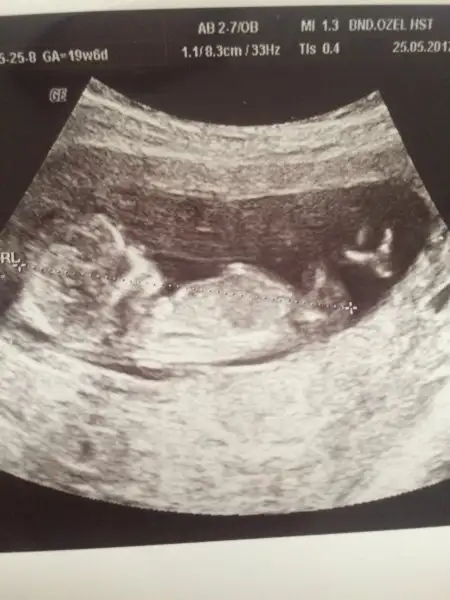

Belliyse muhtemelen erkek demistir dr :) ben resimden bakinca pek anlamiyorum amaBnm cinsiyet belli ama nuba bakın bakıım Bi 12+6da bu usg